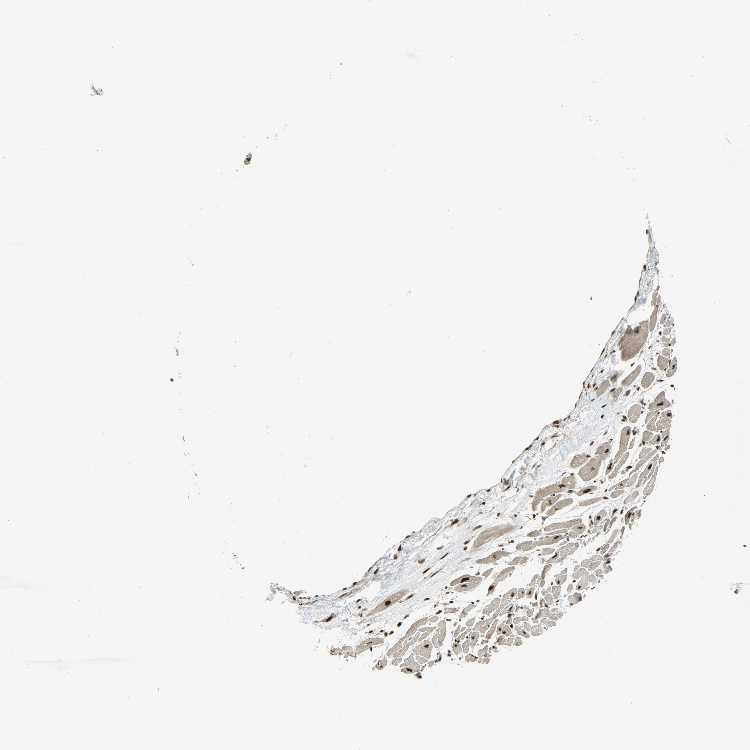

HEART MUSCLE - Antibody stainingi

Antibody staining in the annotated cell types in the current human tissue is reported as not detected, low, medium, or high, based on conventional immunohistochemistry profiling in selected tissues. This score is based on the combination of the staining intensity and fraction of stained cells.

Each image is clickable and will lead to virtual microscopy that enables deeper exploration of all samples and also displays staining intensity scores, fraction scores and subcellular localization as well as patient and tissue information for each sample.

Antibody HPA006111Antibody HPA008884

Cardiomyocytes HighMedium